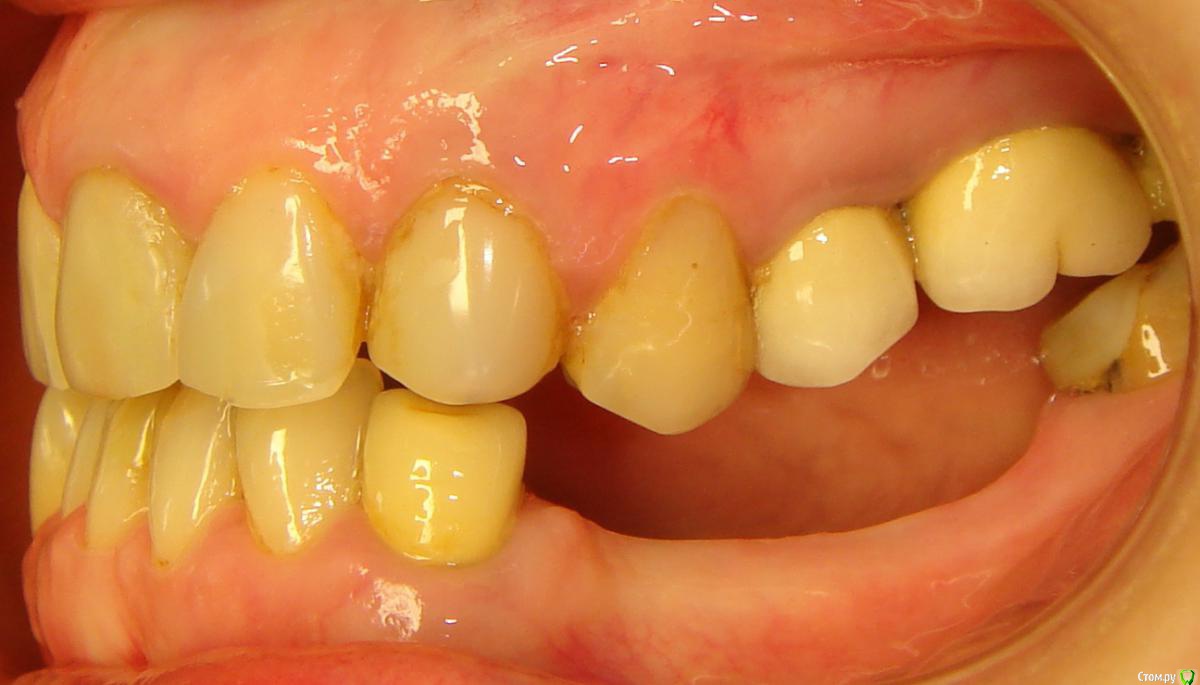

Здравствуйте, Коллеги! Хочу спросить совета по такому случаю. Пациентка 33 года. В детстве удалили 12 зуб, пространство закрыли на съемном аппарате. В подростковом возрасте удалили все остальные отсутствующие зубы. Сейчас носит бюгель. Вопрос такой: заниматься ли мне, как ортодонту формированием полноценного межчелюстного соотношения, или просто решить локальные проблемы и отдать на функциональную реабилитацию ортопеду? И если все-таки заниматься мне, то как??? Лечение такого третьего класса - элементарно для многопетлевой при наличии адекватной опоры, но вот такая адентия заставляет меня сомневаться. Заранее спасибо за ответы!